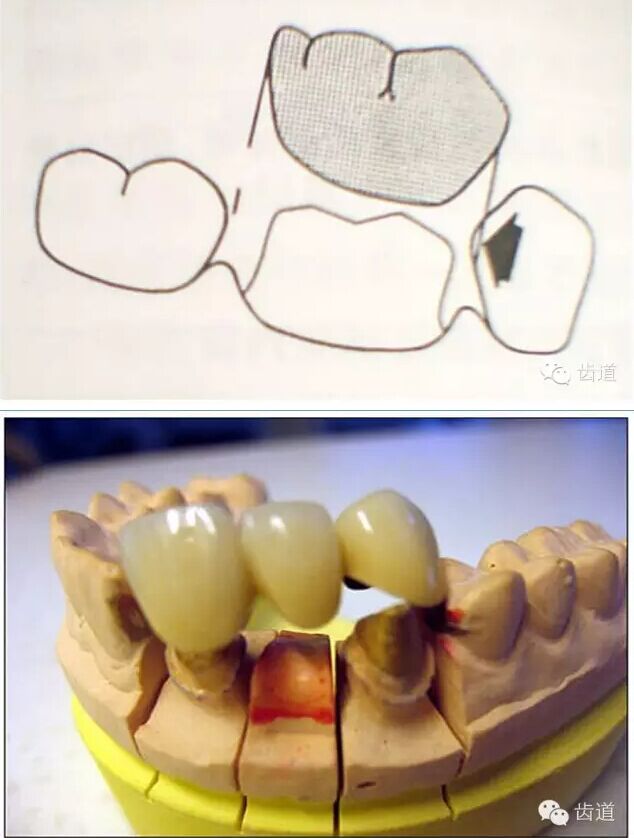

l預(yù)留修復(fù)體的空間

l邊緣的適合性

牙的外形及洞形的幾何形狀:主要是牙體制備出一定聚合角度產(chǎn)生的阻擋作用